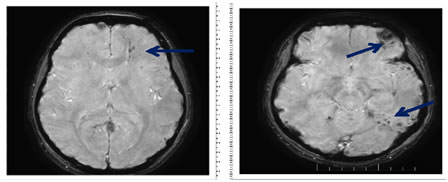

- Diffuse Axonal Injury (Dai)

Diffuse axonal injury (DAI) is the Disruption of the cytoskeletal network and axonal membranes. Axonal damage occurs with axonal rotational acceleration and deceleration movementdue to traumatic effect21 DAI is also known as "shearing injury". Diffuse axonal injury typically consists of several focal white-matter lesions measuring 1-15 mm in a characteristic distribution. 6 Traumatic micro-bleeds are considered to be a radiologic marker for DAI 20,21 Location of DAI are typical, Subcortical and deep white matter are commonly affected. Cortex will be spared. DAI locates in subcortical white matter (mild form), corpus callosum (middle form) andbrainstem (severe form).21 On CT initially often normal. Subcortical white matter, corpus callosum or brain stem may show small hypodense foci which are corresponding to edema of shearing injury. Punctatehemorrhagic lesions may appear as hyperdense foci on CT. (Fig 11) MRI (Fig 12) Magnetic resonance imaging (MRI) is the preferred examination for DAI (particularly with gradient-echo sequences. T2W- image shows multifocal hyperintense lesions at characteristic locations. Especially, hemorrhagic lesions are seen as blooming in SWI sequence. Multifocal hypointense foci on SWI are seen due to susceptibility of blood products.20,21,22

Figure 12: Axial SWAN MRI sequence: A 15-year old boy was presented after a motorcycle accident, shows multiple hemorrhagic foci in the left cerebral hemisphere.